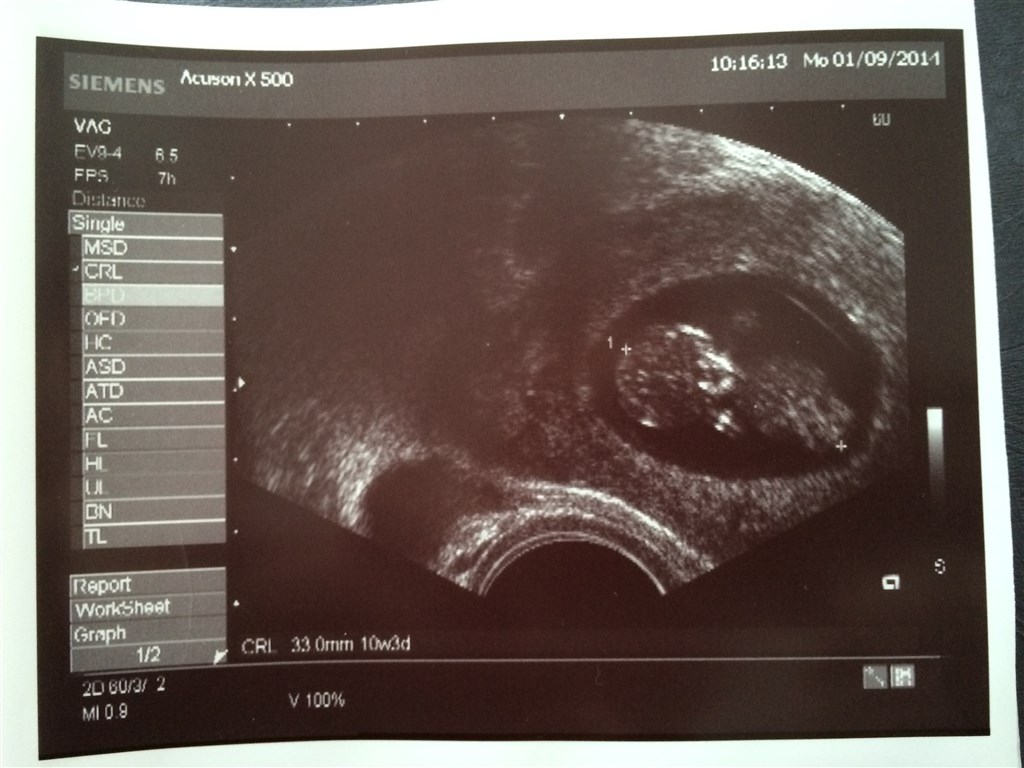

Var til scanning igår, der var det smukkeste hjerte blink.

Blev dog rykket tilbage i termin, er 6+2 idag

Vedhæftede fotos (klik for at se i fuld størrelse)